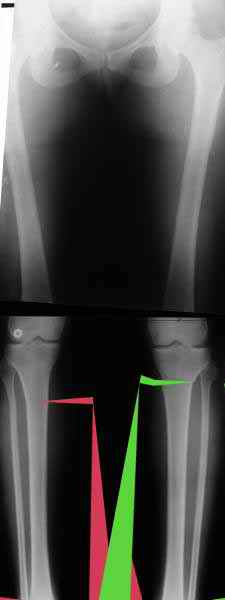

AC> Вот, с учетом и без учета, и на разных уровнях...

Из приведнной схемы не совсеим понял что означают разноцветные линии.

И зачем латерализация периферического фрагмента. Я всегда делаю медиализацию. См схему. И для данного случая медиализация подходит как нельзя лучше.

a> Из приведнной схемы не совсеим понял что означают разноцветные линии.

Черные - это нынешняя механическая ось. Красные - это планируемая правильная ось.

a> И зачем латерализация периферического фрагмента.

;-) Читайте Палея. Стр. 114-115.

a> Я всегда делаю медиализацию. См схему. И для данного случая

Медиализация - это чисто эстетический прием, как я понимаю. Поскольку если делать остеотомию ниже вершины деформации, для восстановления оси надо делать смещение по ширине, в данном случае как раз латерализацию.

А вот на схемке без осей - там на разных уровнях (который правильнее?) устранение варуса чисто открытым клином без медиализации-латерализации. Если как-то так сделать - этого недостаточно будет?